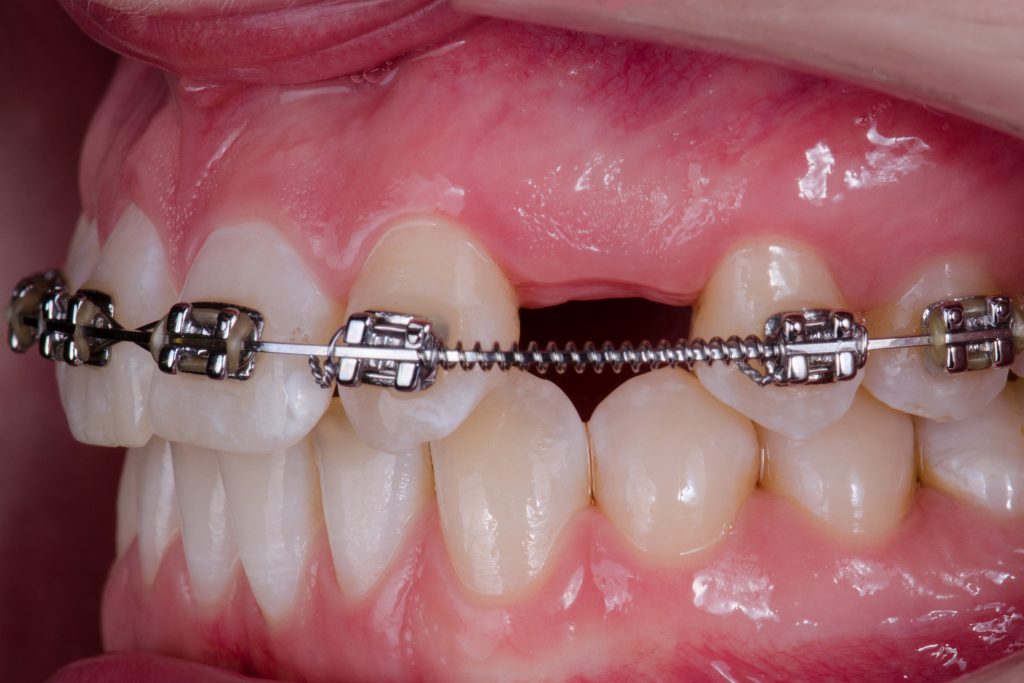

A 24-year-old female patient referred by an orthodontist who resolved the unilateral agenesis of the left upper lateral incisor by mesializing the left upper cuspid and shifting the gap in between teeth 23 and 25. After confirming the free bone corridor between the roots of the cuspid and the first bicuspid, a Straumann BLX RB implant (3.75 mm) was inserted and thin soft tissue buccally augmented with tuberosity connective graft. A sliding island flap on the palatal side relieved tension while suturing both sides of the mucosa. Three months later, the ortho appliance was removed and a temporary crown (Cerasmart) was delivered. All teeth were whitened and after four-month-period, an all-ceramic crown (Katana) was made and fixed. The patient denied and reshaping of the tooth 23. In 3 years, the situation is sthbilized however the prognosis of the tissue covering the tooth 23 is doubtful. Prosthetic part of the treatment done by a.krugova

sufficient bone width in cuspid area